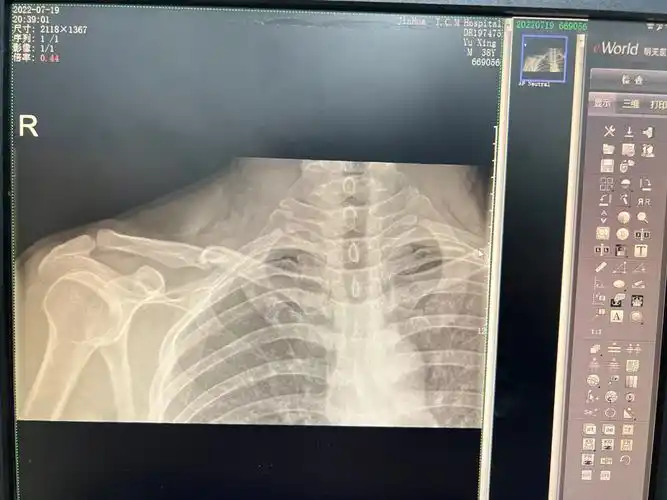

右锁骨远端骨折手术过去一个多月了.

今日手术-右锁骨骨折切开复位内固定